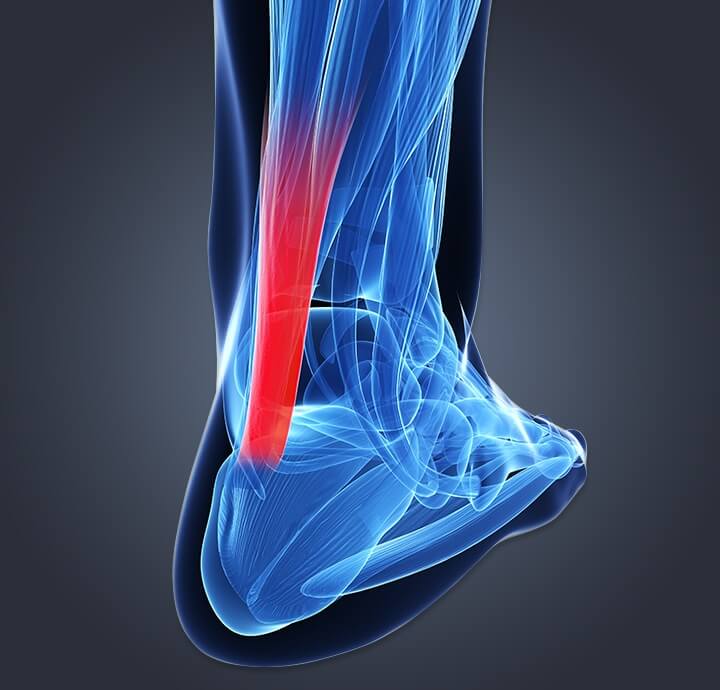

pictures of achilles tendon

💥𝐀𝐜𝐡𝐢𝐥𝐥𝐞𝐬 𝐓𝐞𝐧𝐝𝐢𝐧𝐨𝐩𝐚𝐭𝐡𝐲💥 ——— 👣Achilles tendinopathy describes a …